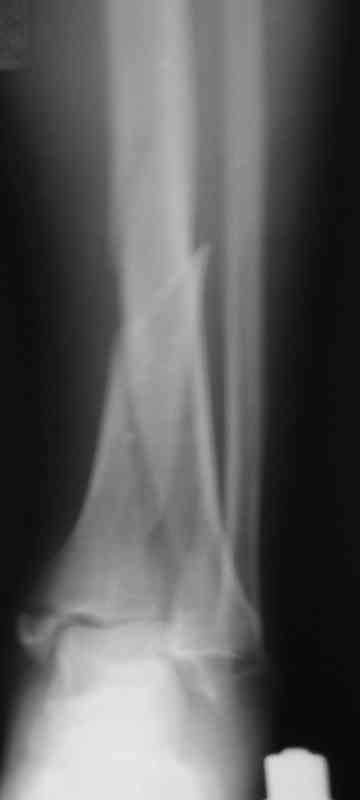

Сегодня прооперировали. Длительность 4-50. Начали как и говорил сверху вниз линейным разрезом - фиксация задне-латерального отломка к проксимальному 2мя винтами, затем "прилепили" к ним передне-медиальный (пришлось повозиться - была интерпозиция и довольно "сложный" винт) - к проксимальному 1 винтом и к задне-латеральному 1 винтом.Кстати на фото видно - у передне-медиального отломка еще осколок в области сустава, несколько смят. Далее началось веселье - второй доступ - задне-наружный к латеральной лодыжке и заднему краю, но оказалось, что задний край больше задне-медиальный (по снимкам было непонятно). Плюс к этому репозиция его мягко говоря сложновата (больной на спине, стол низкий и не поднимается). В общем выставили, фискировали 2мя винтами, на ЭОПе вроде стал, только верх отошел. Латеральную лодыжку заведующий решил интрамедуллярно (не хотел еще винты толкать), сначала 3мм спицей - нестабильно, затем 4мм стержень (не помню по автору) - ОК (кстати в месте перелома мелкая крошка - дефект до 5х7 мм по кортикалу). Ну медиальная лодыжка стандартно - третий разрез - винт 3,5 мм. Визуально все стабильно. На Р-контроле - видна небольшая ступенька заднего края по одному из контуров.

Далее - сейчас нога в пластиковом башмаке (гуманитарная помощь - что-то вроде транспортной иммобилизации - пластик+пневмо), далее заведующий хочет гипсовую повязку до колена. Я предлагаю как иммобилизация аппарат - кольцо - проксимальный метафиз, полукольцо - пятка. По-моему для кожи (оцените на фото), да и для больного лучше. Ваше мнение?

Фото и Р-граммы в приложении

Рентгенограммы

По снимкам до операции задний край находился в правильных взаимоотношениях к передне-медиальной части суставного конца tibia, то есть мог быть фиксирован закрыто спицами или винтом.

Опять фото нет, только рентгенограммы были.

Вообще, аппарат тут вполне можно, только фиксация стопы избыточна, разве что до заживления раны. Аппарат тут нужен в той же роли, что нейтрализующая пластина.

Нельзя ли попросить снимки именно голеностопного сустава. Представлены снимки голени в нижней трети.Сустав фактичеси не виден.

Александр, если вы имеете в виду послеоперационные Р-граммы - то это все что есть. А сустав виден достаточно, чтобы оценить то что есть

Приветствую, Антон

> Александр, если вы имеете в виду послеоперационные Р-граммы - то это

> все что есть.

Да, послеоперационные.

>А сустав виден достаточно, чтобы оценить то что есть

Как скажете, хотя суставная поверхность не совсем видна.

Вы представили снимок голени в нижней трети. На сустав луч упал косо, это искажает.

Есть подозрение, что имеется ступенька заднего края, внутренняя лодыжка оттопырена. Взаимоотношения в суставе важнее, чем точная репзиция диафиза.